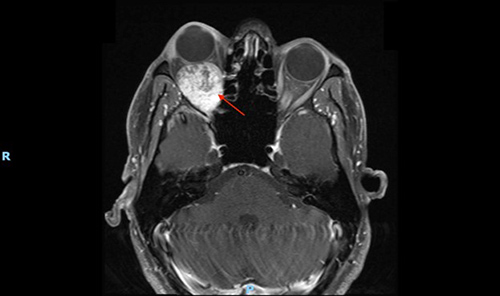

Benign right orbital tumor, pushing the eye forward

(Photo courtesy of Dr. Gudis)

The ORBIT classification system, which is adapted from the CHEER framework, uses CT and MRI imaging to determine the location of the tumor, looking specifically at the epicenter of the tumor and its greatest extension. Class I tumors, the lowest risk classification, are extraconal, meaning they are outside of the muscles in the eye socket. The ORBIT system goes up to class V tumors, which can be extraconal or intraconal but have intracranial extension through the superior orbital fissure, indicating that they are the most complicated and highest risk. At a higher classification it might be necessary to forego an endoscopic technique or to combine it with another approach, Dr. Gudis says.